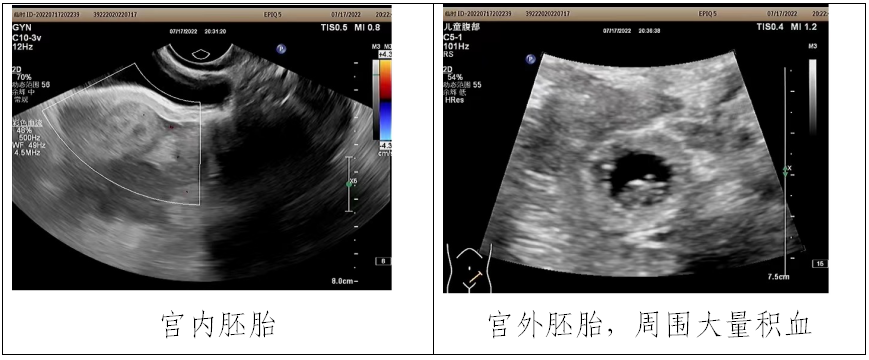

据悉,该名患者于7周前在某大型医院生殖中心进行了第三次胚胎移植术,并曾两次在其他医院彩超检查提示为宫内早孕。7月17日晚,患者因腹痛半天难忍、全身苍白、冷汗不止到我院就诊,入院后呈休克体征,情况不容乐观。面对不明病因导致的危急病情,接诊医务人员临危不乱,立即开启绿色通道,在进行抗休克治疗的同时争分夺秒寻找分析病因,最后彩超医生在大量的盆腹腔积液中找到了非常隐匿的异位妊娠病灶,诊断为:宫内宫外复合妊娠、腹腔内出血、失血性休克。

该患者此前曾2次胚胎移植失败,患者和家属对此次妊娠期待非常高,因此,为在危急情况下同时挽救患者生命和保住宫内妊娠,妇科主任高洪波带领妇科团队为患者制定了“免充气腹腔镜手术探查”手术方案,通过微创手段,避免传统腹腔镜气腹压对胚胎的影响。最后,在妇科、麻醉科、手术室的紧密配合下,手术顺利完成。术后患者恢复良好,已于7月22日出院,后经2次复查彩超,提示宫内胚胎发育正常。